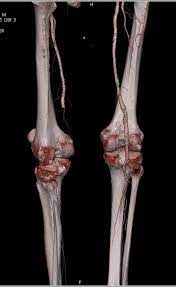

Kāda izskatīsies pacienta kreisā kāja, ja pacients sūdzas par sāpēm kājā vairākas stundas un CTA ir šāds?

Peripheral Vascular Disease (PVD) with Left Superficial Femoral Artery  (SFA) Occlusion: https://www.ctisus.com/teachingfiles/vascular/431534